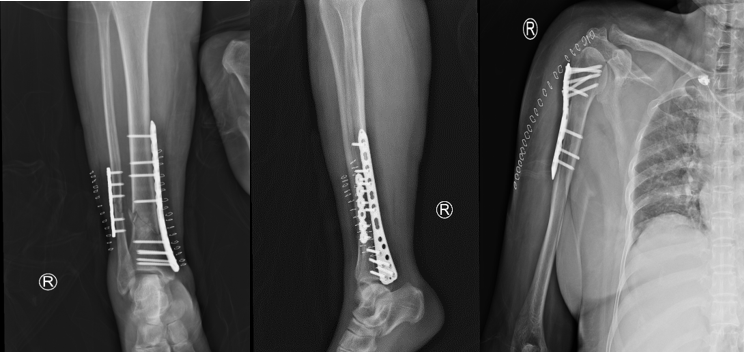

病情稍有稳定后,其它治疗迫在眉睫,如不能抓紧手术,严重的并发症将使患者再次陷入危险之中。骨科何罕亮副主任医师综合考虑患者情况,决定实施分期手术。第一次先行肱骨骨折切开复位内固定术 +胫腓骨骨折切开复位内固定术,第二次视患者情况择期行全髋关节置换术。

第一次手术的关键在于速度要快!这一次手术一共需要处理两个部位、三处骨折,为了尽量减少对患者的影响,手术要求在短时间内完成。何罕亮医师团队术前仔细研究病情,术中精细操作,全部手术在3小时内顺利完成,手术中出血仅130ml,术后复查X线显示骨折对位对线良好。

第一次术后复查X线